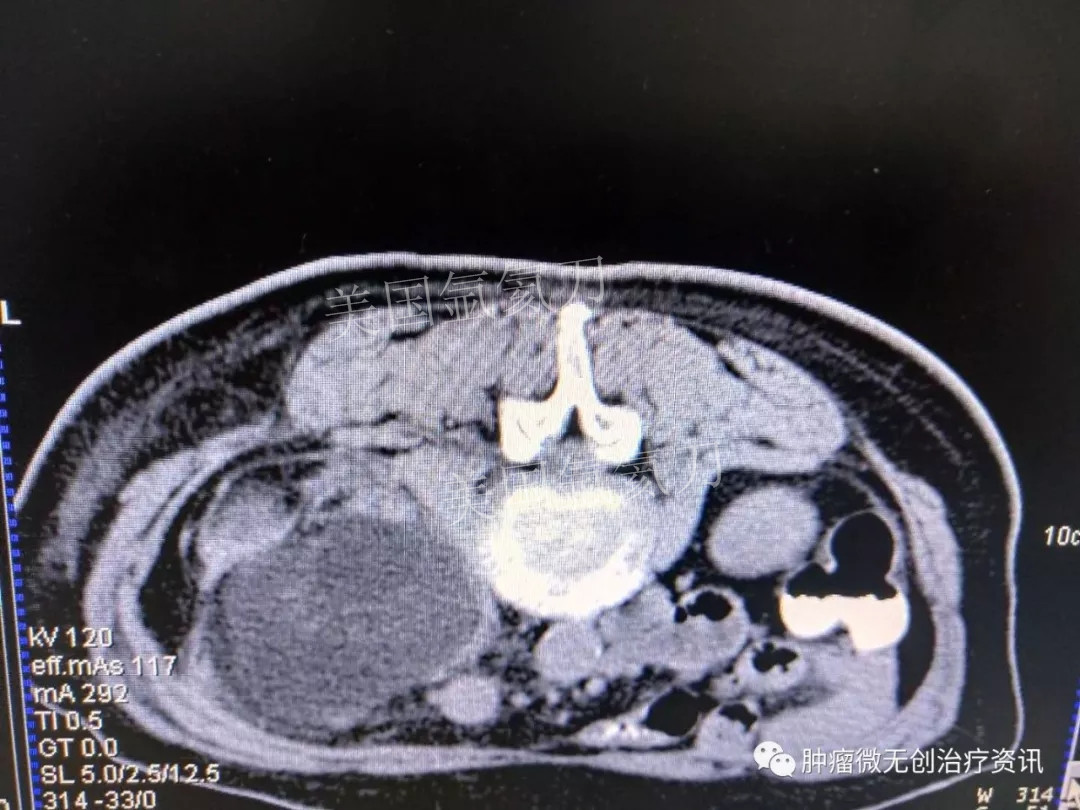

腹膜后脂肪肉瘤氩氦刀冷冻消融治疗——中国人民解放军第307医院

66岁女性患者,因腹膜后脂肪肉瘤,入住于中国人民解放军第307医院肿瘤微创治疗科。结合患者情况,行氩氦刀冷冻消融治疗。